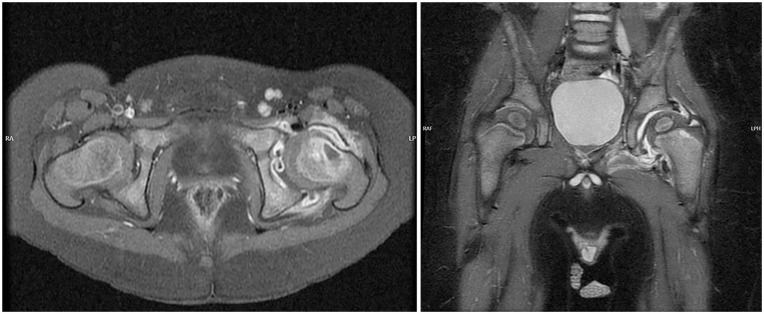

正确的诊断和治疗化脓性关节炎(SA)是必不可少的,以获得满意的结果,避免终身后果。诊断感染性关节炎并不总是那么容易,这就是为什么人们一直在寻找新的生物标志物。另一个诊断上的困难是由于金氏菌引起的脓毒性关节炎的增加,它与典型的金黄色葡萄球菌感染没有相同的体征和症状。磁共振成像在脓毒性关节炎的诊断中发挥着越来越重要的作用,许多研究都集中在这方面,特别是对相关病理的研究。已经发表了许多关于脓毒性关节炎的微创治疗的研究,尽管有证据表明应该谨慎对待结果。虽然大多数已发表的研究集中在髋关节和膝关节,但最近也有关于上肢、足部和踝关节SA的研究。最后,由于其病因不同且诊断难度较大,文献也关注了幼儿SA。

Correct diagnosis and treatment of septic arthritis (SA) are essential to achieve satisfactory results and avoid lifelong consequences. Diagnosing septic arthritis is not always easy, which is why new biomarkers have been sought. Another difficulty in diagnosis is the increase in septic arthritis due to Kingella Kingae, which does not show the same signs and symptoms as classic Staphylococcus aureus infections. Increasingly, magnetic resonance imaging plays a more fundamental role in diagnosing septic arthritis, and many studies are focused on this line, especially for the study of associated pathologies. Numerous studies have been published on less invasive treatments for septic arthritis, although the evidence suggests that the results should be taken cautiously. Although most of the published studies focus on the hip and knee, there have also been recent publications on SA in the upper limb, foot, and ankle. Finally, the literature also pays attention to SA in young children due to its different etiology and the greater difficulties in its diagnosis.